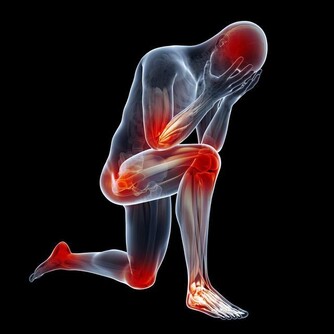

氣溫驟降時,腦血管疾病發病者明顯增加。劉霞發病時,正好遇到兩大誘因,一是天氣轉冷,二是深夜用熱水泡腳,都可能令血管受到強烈刺激,一定程度上誘發疾病。因此,有腦血管基礎性疾病的市民,近期應注意防寒保暖,避免身體遭受冷暖刺激。少用過熱的水洗澡、泡腳,少喝酒,避免情緒激動。同時,還應定時對身體進行全面檢查。

冬天很多人喜歡泡熱水腳,但是泡腳也是有養生禁忌的,熱水泡腳的六個禁忌您不可不知。

熱水泡腳的六個禁忌人們都懂得一個常識,那就是腳暖身體就暖,腳底是有很多穴位的,這些穴位打通,全身的經絡就打通,於是人們就更加知道泡腳的好處,尤其是在寒冷的冬天,睡覺前弄上一盆熱熱的水,泡上15分鐘以上的腳,會感覺一天的疲勞都消失了,也有助於更快的入睡和更好的睡眠質量,試想一下,如果寒冷的冬天,冰涼的腳即使鑽進被窩,也很難立即暖和起來,而腳睡不暖,身體就感覺寒冷,怎麼可能睡得好,還會輾轉反側,夜不能寐,因此,腳暖是很重要的。

可是泡腳雖然好處多多,在過程中還是有很多的注意事項,任何一件事情只有掌握好度,才是最好的,就像身體一樣也是最講究平衡的。那泡腳中有哪些禁忌呢?聽我一一道來。

1、切忌溫度過高。

泡腳是通過水溫讓腳迅速的暖和起來,但是千萬水溫不能太高,因為太高的水溫會燙傷腳部的皮膚,輕者會發紅,重者會起水泡,我們經常會看到因為水溫過熱,皮膚被燙傷的情況。如果是糖尿病的患者更要注意水的溫度,因為他們對溫度的感應不敏感,更容易被燙傷。

3、心臟病病人和低血壓者當心暈厥。

這類病人泡腳時要格外小心,一是水溫不可過高,二是泡腳時間不能過長,因為用熱水泡腳后,會迅速導致人體血管擴張,全身血液會由重要臟器流向體表,因此很容易使心臟、大腦等重要器官缺血缺氧,因此對於有心臟病、低血壓的人群來說,就會增加他們發病的危險。

5、老年人泡腳的時間不可過長。

因為老年人整個機體的體能和體質在下降,身體相對更加的虛弱,如果泡腳時間過長,會引起出汗、心慌等癥狀,還容易誘發一些疾病。因此,老年人建議泡腳的時間不超過20分鐘。